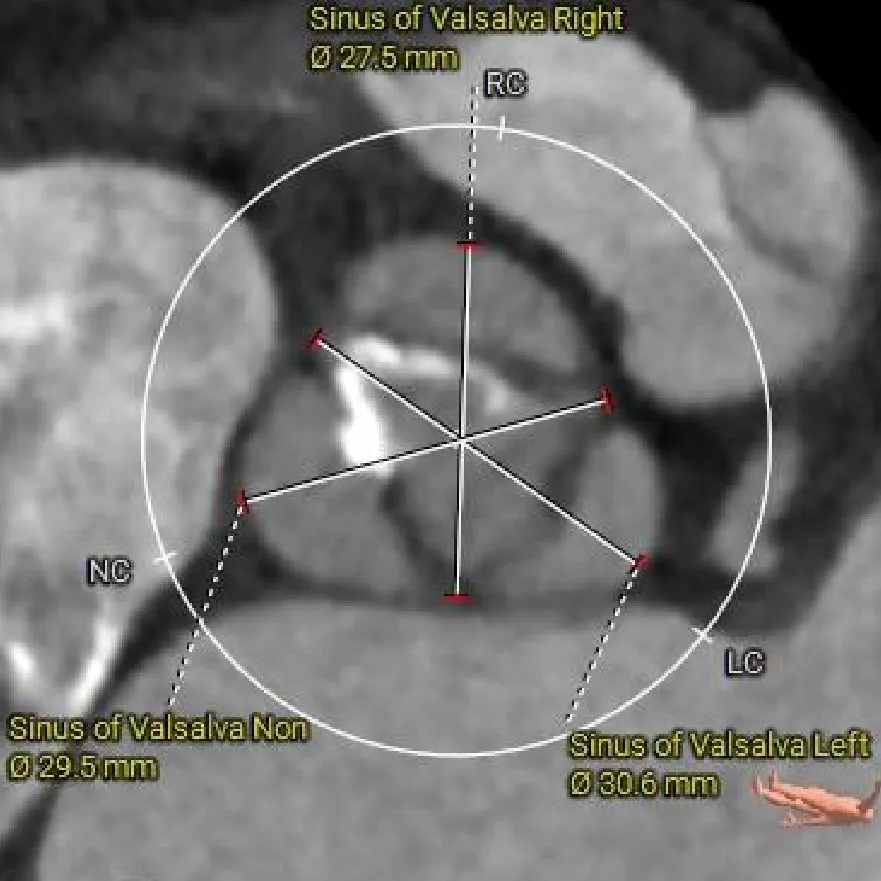

L-30.6mm R-27.5mm

N-29.5mm

主动脉根部测量

Super-Annulus

2mm 20.5mm

4mm 21.3mm

6mm 21.3mm

8mm 20.8mm

10mm 21.4mm

12mm 20.8mm